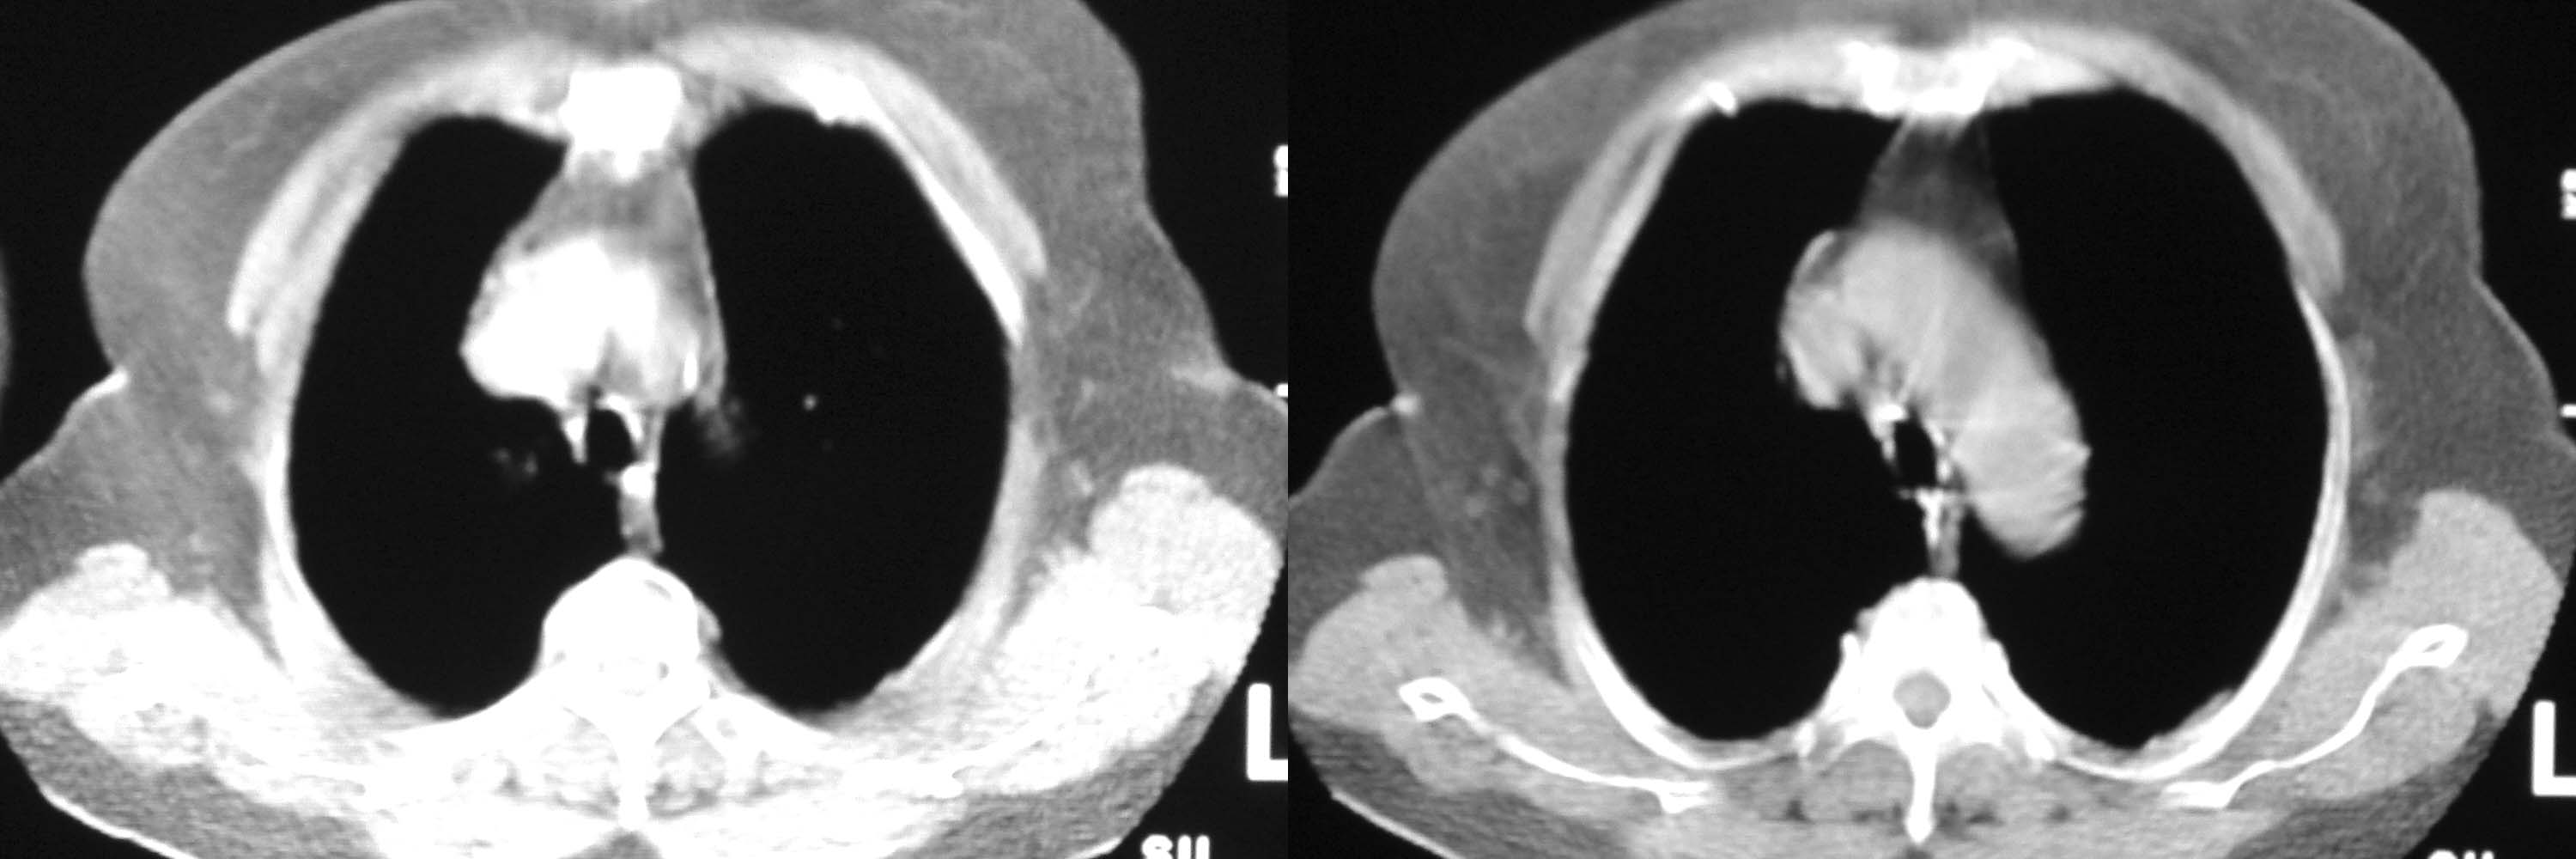

女78岁咳嗽咳痰无咳血平片报右上肺不张、慢支、肺气肿、请老师们帮忙看看,箭头所指是什么?是占位吗?有肺气肿吗?谢谢

箭头所指----多考虑-----右头臂静脉旁淋巴结钙化

可能是逾曲的头臂血管

可能是纡曲的头臂血管——支持。

可能是纡曲的头臂血管——支持。建议增强

箭头所指考虑血管影

箭头所指考虑血管影;纵隔内及双肺门区多发淋巴结钙化;不支持肺气肿。

箭头所指考虑血管影(头臂血管);纵隔内及双肺门区多发淋巴结钙化;不支持肺气肿。